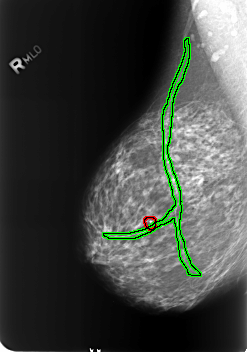

B_3239_1.RIGHT_MLO

FILE: B_3239_1.RIGHT_MLO.OVERLAY

TOTAL_ABNORMALITIES 2

ABNORMALITY 1

LESION_TYPE CALCIFICATION TYPE LUCENT_CENTER DISTRIBUTION N/A

ASSESSMENT 2

SUBTLETY 4

PATHOLOGY BENIGN_WITHOUT_CALLBACK

TOTAL_OUTLINES 1

BOUNDARY

ABNORMALITY 2

LESION_TYPE CALCIFICATION TYPE VASCULAR DISTRIBUTION N/A